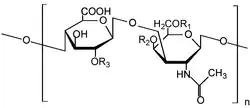

The normal volume of synovial fluid obviously varies from joint to joint. Normal synovial fluid contains 3–4 mg/ml hyaluronan (hyaluronic acid). [10] Hyaluronan is synthesized by the synovial membrane and secreted into the joint cavity to increase the viscosity and elasticity of articular cartilages and to lubricate the surfaces between synovium and cartilage.[11] Synovial fluid includes lubricin (also known as PRG4) as a second lubricating component, secreted by synovial fibroblasts.[12] It has an essential role in so-called boundary-layer lubrication, which reduces friction between the surface of cartilage. In addition, it helps regulate synovial cell growth.[13] It also includes phagocytic cells that remove microbes and the debris that results from normal wear and tear in the joint. And it is related to the change of pH in the synovial fluid.[14]

Hyaluronic acid

Hyaluronan is an anionic, nonsulfated glycosaminoglycan which exist in connective, epithelial, and neural tissues. It is unique and can be very large, with its high molecular weight often close to the millions.[29] In the extracellular matrix, hyaluronan has a essential role in cell proliferation and migration, and may also be involved in the progression of some malignant tumors.[30]. Hyaluronic acid as a component synovial fluid is commonly injected into the joint as a treatment for osteoarthritis. It has not been proven to generate benefit and has potential side effects.[31] In 2007, the European Medicines Agency extended its approval of Hylan GF-20 as a treatment for ankle and shoulder osteoarthritis pain.[32]